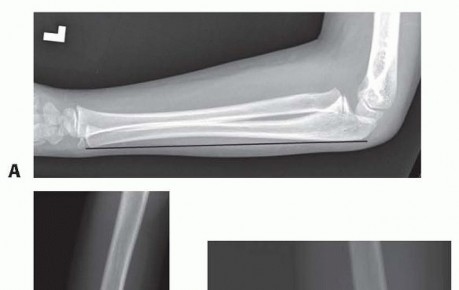

Chapter 3 Intramedullary Fixation of Forearm Shaft Fractures Charles T. Mehlman DEFINITION Forearm shaft frac…